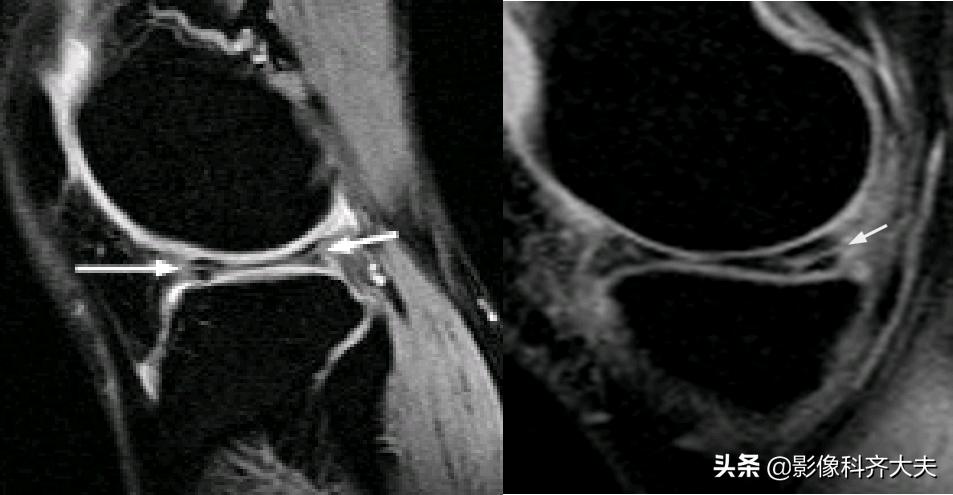

水平方向撕裂

垂直方向撕裂

星芒状撕裂

瓣状撕裂

桶柄状撕裂示意图

半月板撕裂后移位